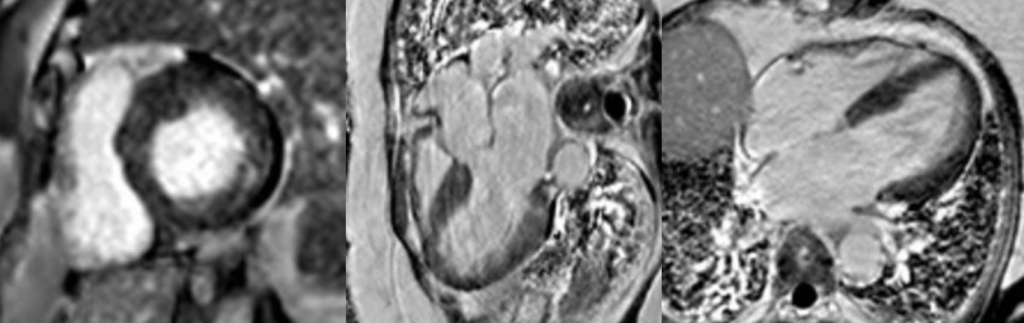

Native T1 mapping images

Short-axis and long-axis native T1 maps demonstrating diffusely reduced myocardial T1 values throughout the left ventricle, consistent with intracellular lipid accumulation.

Late gadolinium enhancement images

Short-axis and long-axis late gadolinium enhancement sequences demonstrating focal mid-wall pathological enhancement involving the basal inferolateral wall.